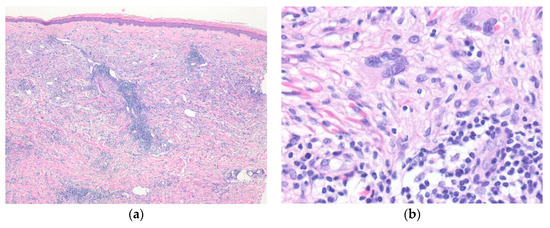

4. Epithelioid Smooth Muscle, Perivascular, and Vascular Tumors

4.1. Cutaneous Smooth Muscle Tumors